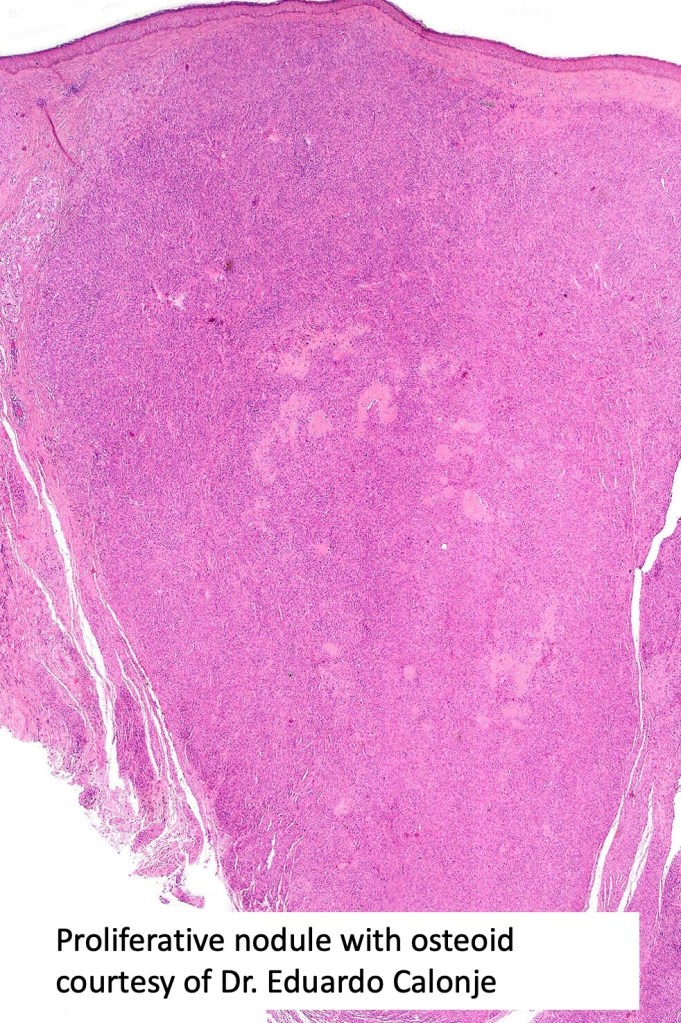

•The nodule generally merges with the adjacent nevus but sometimes it can be sharply circumscribed

•Spindle cell, small blue cell, blue nevus-like features, Spitzoid & proliferative nodules with mesenchymal differentiation (myofibroblastic, chondroid & osteoid) can be seen